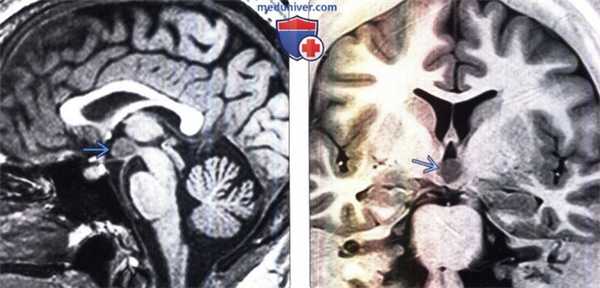

(Слева) МРТ, Т1-ВИ, сагиттальный срез: малые размеры гипофиза и отсутствие его воронки. Гиперинтенсивная эктопированная задняя доля гипофиза расположена на срединном возвышении. Мозолистое тело также дисморфично, валик которого имеет характерные малые размеры.

(Справа) МРТ, Т2-ВИ, корональный срез: у этого же пациента также определяются перивентрикулярная узловая гетеротопия серого вещества слева и дисплазия серого вещества нижних отделов височной доли. Киста хориоидальной щели справа, вероятно, не связана с основной патологией.

(Слева) MPT, Т1 -ВИ, сагиттальный срез: у пациента с септо-оптической дисплазией визуализируется яркая эктопированная задняя доля гипофиза . Обра тите внимание на небольшой зрительный перекрест и низкое расположение сводов головного мозга .

(Справа) МРТ, Т1-ВИ, сагиттальный срез: у пациента с удвоением гипофиза визуализируются утолщение дна турецкого седла и слияние серого бугра с сосцевидными телами (тубероммаммиллярное слияние). Обратите внимание на отсутствие по срединной линии турецкого седла и воронки гипофиза.